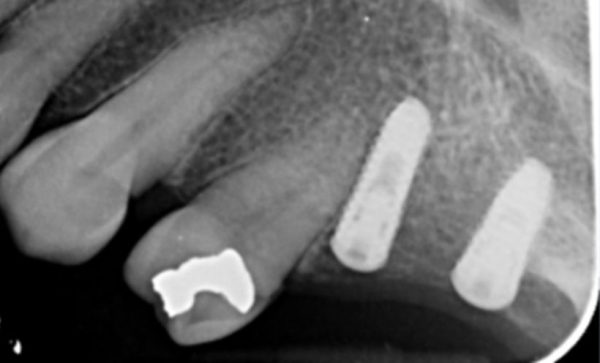

Case 48